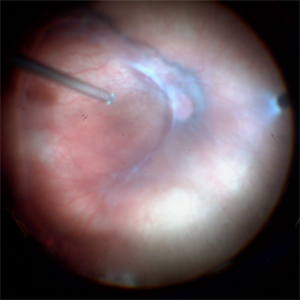

Traumatic Vitreous hemmorrhage in a 4-month-old baby

Nov 23 2022 by Alexandre Grandinetti, MD, PhD

This is a intraoperatory picture taken during a vitrectomy due to dense vitreous hemorrhage

Photographer: Alexandre Grandinetti

Imaging device: Ngenuity 3D

Condition/keywords: hemorrhage, vitreous